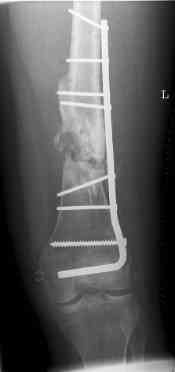

16 yr old boy, high energy motorcycle trauma trauma in July 2005 with:

july 05: LISS femur, LCP plate tibia, double recon. plate post. acetabulum

oct 05: cancellous bone graft femur

aug 06: blade plate + bone graft

nov 06: revision blade plate

feb 07: retrograde nail + bone graft + BMP

may 07: dynamisation nail

sept 07: locking screw removal (max. dynamisation reached)

nov 07: persistant non-union distal femur; other fractures healed uneventfully.

All with gradual/partial weightbearing etc. Currently 50-100% weight bearing, no pain.

Soft tissues are intact. No smoking or diabetes.CRP <2

What would you do?